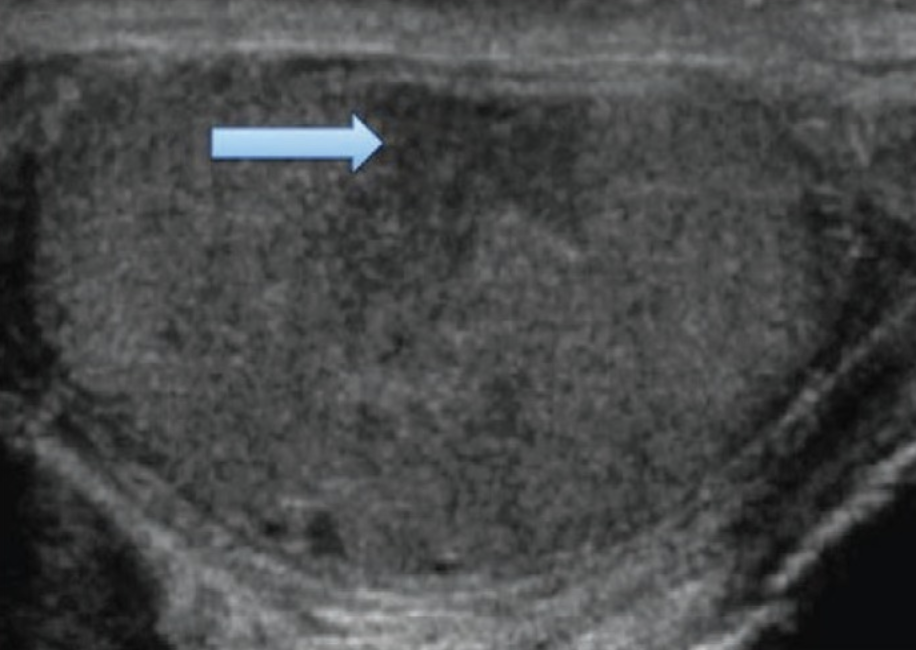

Intratesticular Hematoma (indicated by blue arrow). Source: Bowen & Gonzalez, 2014.

- Findings: Well-defined, hypoechoic or heterogeneous intratesticular lesion with no internal flow and intact tunica albuginea. Testicular vascularity is preserved.

- Sensitivity: 71%; Specificity: 77% (Guichard et al., 2008)

- Management: Many ITHs can be managed conservatively. However, if concern for expanding hematoma or severe pain, surgical exploration may be warranted.